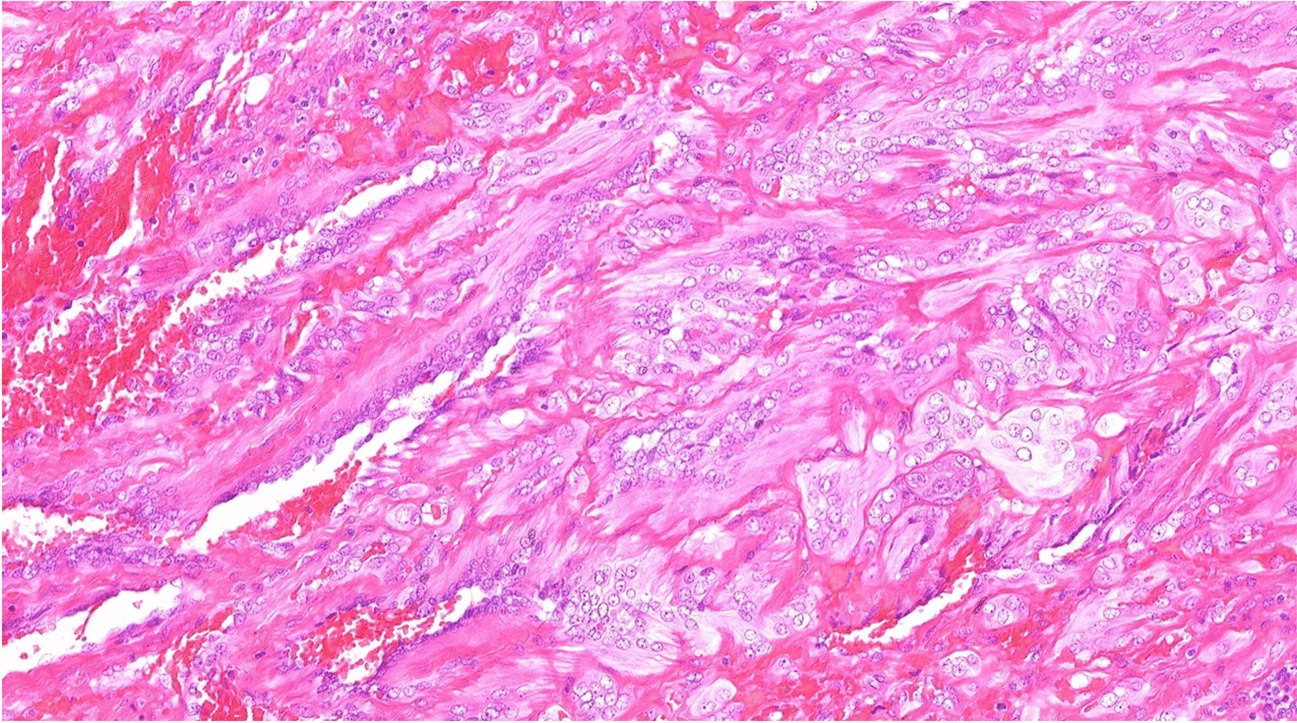

The subgroup characterized by CRTC1::TRIM11 fusion is relatively well-documented, with over 40 reported cases so far [2, 5, 7, 8]. Typically found on the distal extremities and trunk, this tumor presents as a well-defined dermal nodule, occasionally extending into subcutis. Almost all cases lacked an intraepidermal component apart from one case which, most likely as a result of an upward growth of a primarily dermal tumor, exhibited junctional nests of tumor cells, similar to what has been described in rare cases of clear cell sarcoma [1315]. Individual cases have been observed in submucosal regions [5]. The tumor consists of short intersecting fascicles or nests of relatively uniform epithelioid to spindle cells with eosinophilic cytoplasm, moderate to severe atypia, prominent nucleoli, and limited mitotic activity (< 5 mitoses/10 HPF), without atypical forms (Fig. 1). Binucleated or multinucleated cells are occasionally observed, yet wreath-like multinucleated giant cells, which can be observed in clear cell sarcoma, are absent. Small areas of necrosis are infrequently detected. Immunohistochemically, the tumor consistently exhibits positivity for SOX10 and in approximately 80% of cases demonstrates expression of S100 protein, albeit often limited in extent. Furthermore, at least 60% of reported cases show positivity for HMB-45 and Melan A, with at least one of these markers being positive in 80% of cases [2, 5, 7].

Fig. 1

A, B CRTC1::TRIM11-rearranged tumor is usually composed of short intersecting fascicles or nests of epithelioid to spindle cells with eosinophilic cytoplasm, prominent nucleoli, and minimal mitotic activity (< 5 mitoses/10 HPF), without atypical forms